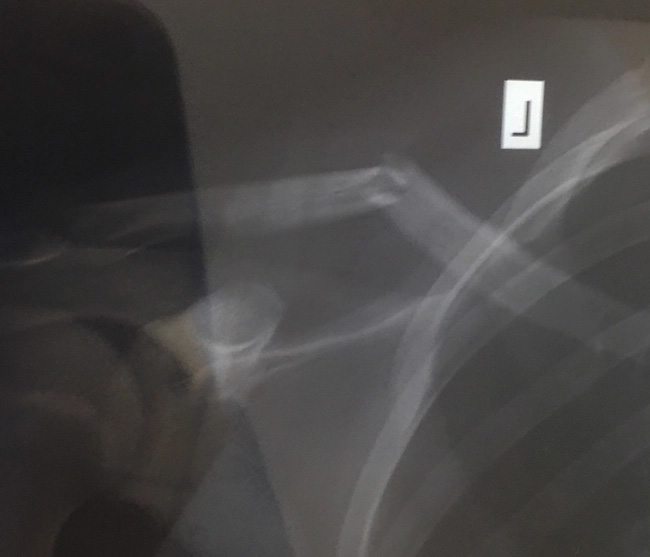

Về cánh tay bị gãy, người thân của cậu bé cho biết, hôm 27/6, trên đường đi học võ trở về Hải An bị tai nạn giao thông, cháu gãy xương quai xanh phải bó cố định.

"Cháu tôi vừa cởi bỏ bộ giáp định hình xương gãy chưa được 1 tuần, tay còn chưa khỏi hẳn mà cháu dám liều mình nhảy xuống sông cứu người chết đuối. Tôi thương cháu nhưng cũng phấn khởi vì nuôi dạy cháu thành người, biết làm việc có đạo lý, có ích" - bà ngoại của Hải An phấn khởi.

Cậu bé mới bị tai nạn giao thông